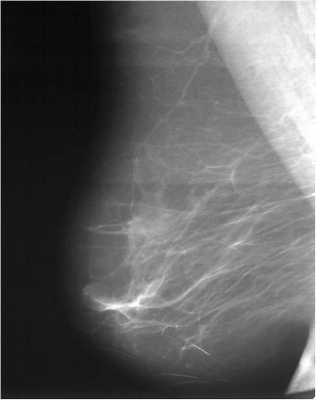

Для выявления злокачественных опухолей молочной железы существует определенный алгоритм диагностики, и его первичный элемент — маммографический скрининг. Чувствительность этого метода диагностики для опухолей от 2 мм до 5 мм составляет около 85%. Маммографическое исследование выполняют в двух проекциях.